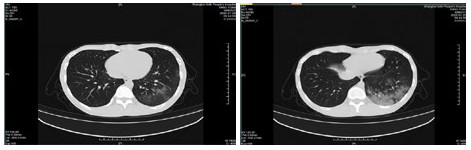

| 图 6 患者,女性,55岁,既往体健,沪籍,无明确武汉流行病学接触史。发热6 d,伴咳嗽,体温39.4℃,伴肌肉酸痛,流感病毒A型IgM阳性,抗柯萨奇病毒IgM阳性,新型冠状病毒核酸检测阴性。肺部CT提示双肺散在磨玻璃结节,部分贴近胸膜。诊断甲型流感病毒性肺炎 Fig 6 Case 6, female, 55 years old, born in Shanghai, was physically healthy, and had no clear history of epidemic exposure of Wuhan. She had fever for 6 days, body temperature was 39.4 ℃, with cough, muscle ache, positive influenza A IgM and anti Coxsackie IgM, negative novel coronavirus nucleic acid test. Lung CT showed ground glass nodules were scattered in bilateral lungs, some of which were close to pleura. She was diagnosed as influenza A virus pneumonia |

| 图 7 患者,女性,36岁,沪籍,有武汉流行病学接触史。发热8 d伴咳嗽,咳痰,有头胀痛,体温38.5℃, 白细胞总数21.8×109/L,淋巴细胞计数10.4%,甲型流感筛查阴性,流感病毒B型IgM阳性,新型冠状病毒核酸检测2次阴性。肺部CT提示双肺多发团片影,实变及磨玻璃结节,伴支气管充气征。诊断乙型流感病毒性肺炎 Fig 7 Case 7, female, 36 years old, born in Shanghai, with a history of epidemic exposure of Wuhan. She had fever for 8 days with cough, expectoration, head pain, body temperature of 38.5℃, total white blood cells of 21.8×109/L, lymphocyte count of 10.4%, negative influenza A virus screening, positive influenza B IgM, and negative novel coronavirus nucleic acid test for twice. Lung CT showed multiple mass shadows, consolidation and ground glass nodule in both lungs, accompanied by bronchiectasis. She was diagnosed as influenza B pneumonia |